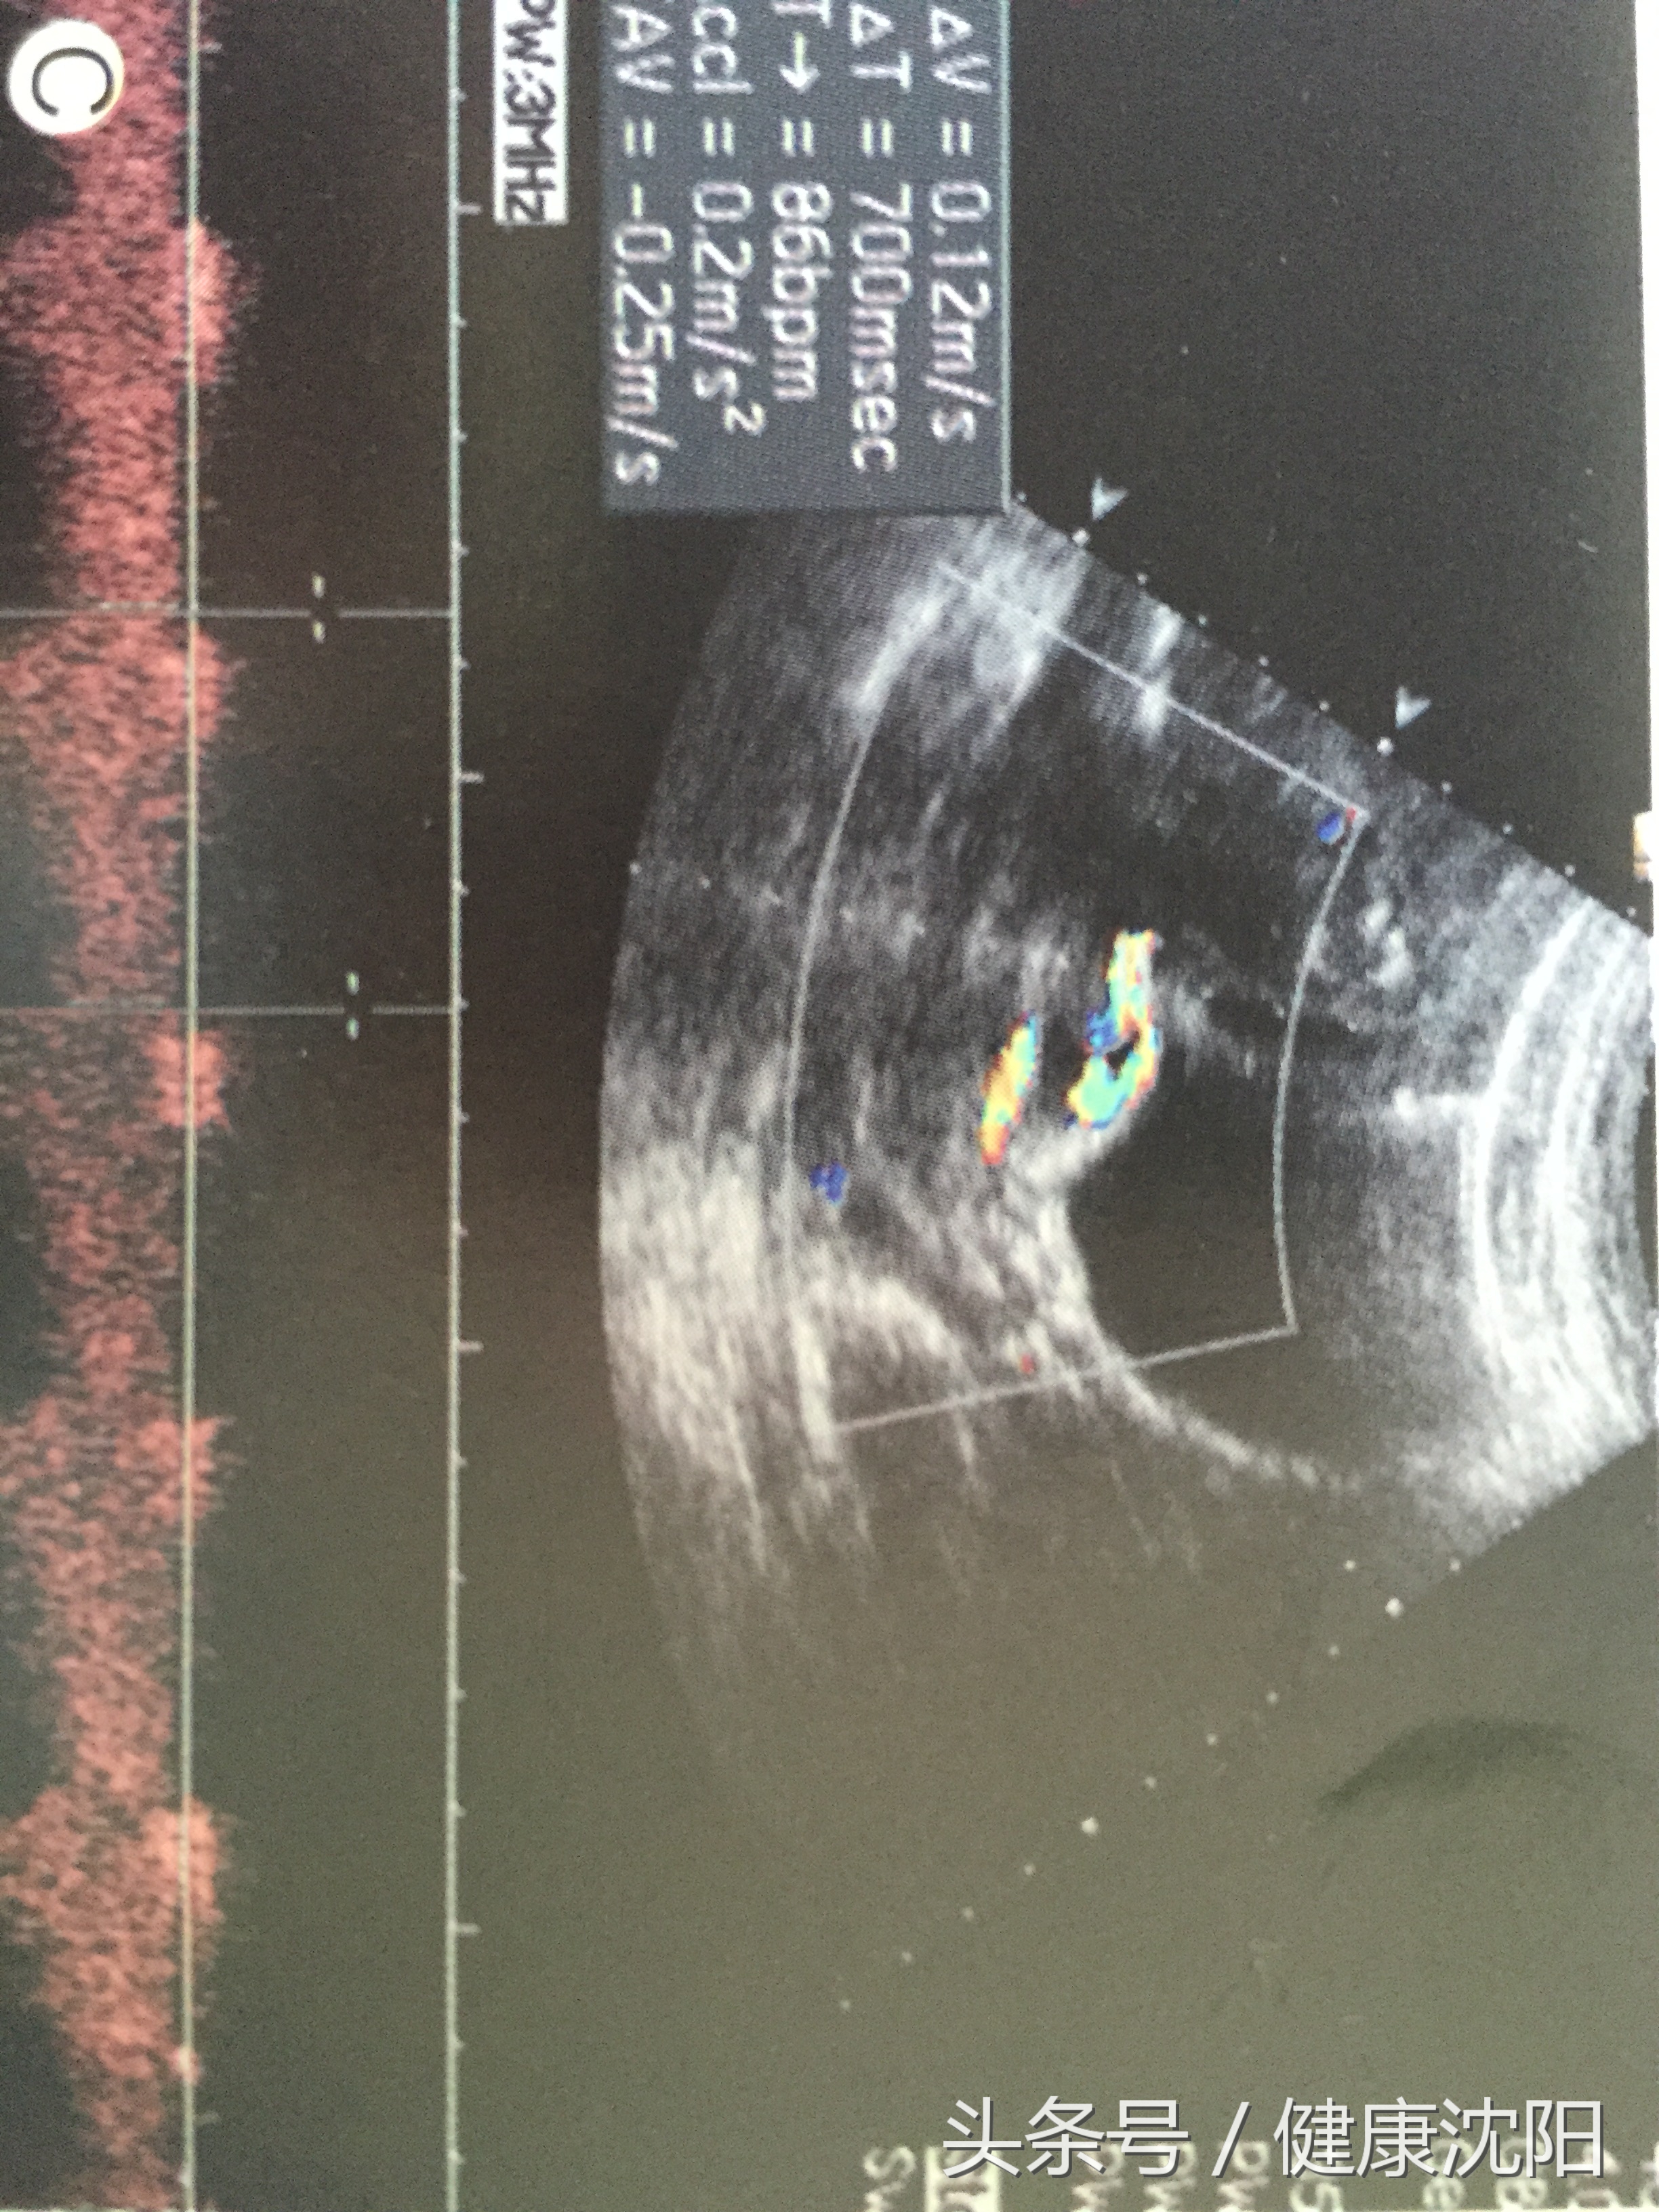

产前超声图像特征明显,表现为宫颈内口上方固定不变的条管状血管回声,呈单直条型或双直条型而缺乏螺旋,血管表面无Wharton胶包裹,或横跨宫颈内口,或接近宫颈内口,叠加CDFI亦可清晰显示宫颈内口上方的直条型血管,脉冲多普勒可探测到与胎儿心率一致的血管搏动。血管前置的产前诊断率与检查时孕周大小、检查者的经验有关。有研究表明,中孕期是诊断血管前置的较佳时间段。

频谱多普勒或彩色多普勒对诊断血管前置极其有用,当疑宫颈内口有胎膜脐带血管时,彩色多普勒超声不仅可直接显示呈扇形分布的帆状脐带入口的胎膜血管或连接主副胎盘之间的胎膜血管,而且可获得典型的胎儿脐动脉频谱,故彩色多普勒超声可明确诊断血管前置。